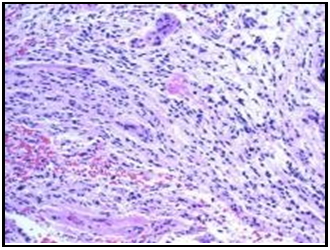

Visceral Leishmaniasis in A Patient with Multiple Myeloma: Casuality or Causality?